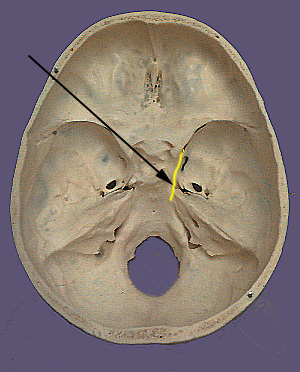

Cranium CN III

CN III. Oculomotor Nerve

The oculomotor nerve originates from motor neurons in the oculomotor  (somatomotor) and Edinger-Westphal (visceral motor) nuclei in the brainstem. Nerve cell bodies in this region give rise to axons that exit the ventral surface of the brainstem as the oculomotor nerve.  The nerve passes through the two layers of the dura mater including the  lateral wall of the cavernous sinus and then enters the superior orbital fissure to access the orbit. The somatomotor component of the nerve divides into a superior and inferior division. The superior division supplies the levator palpebrae superioris and superior rectus muscles. The inferior division supplies the medial rectus, inferior rectus and inferior oblique muscles. The visceromotor or parasympathetic component of the oculomotor nerve travels with inferior division.  In the orbit the inferior division sends branches that enter the ciliary ganglion where they form functional contacts (synapses) with the ganglion cells. The ganglion cells send nerve fibers into the back of the eye where they travel to ultimately innervate the ciliary muscle and the constrictor pupillae muscle.